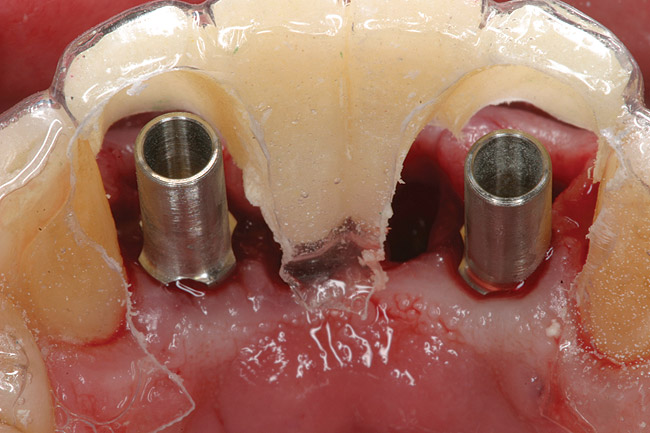

Preoperatively, 1 g of amoxicillin was administered. Using local anesthesia (lidocaine 1:100,000 epinephrine), extractions of teeth No. 23 to No. 26 were performed without raising a flap and with gentle luxation to preserve the remaining facial osseous plate. The sockets were curetted prior to implant placement. A vacuum-formed surgical guide, fabricated based on a diagnostic wax-up of the desired tooth positions for the subsequent fixed prosthesis, was used during implant placement. Osteotomies were performed at sites No. 23 and No. 26 and positioned toward the lingual aspects of the sockets (Figure 3A and Figure 3B). Two tapered implants (OsseoTite™ 313, BIOMET 3i™, Palm Beach Gardens, FL) measuring 3.25 mm x 13 mm were placed. Conical prosthetic abutments (3-mm height) were used to facilitate joining the two implants in a screw-retained fixed partial denture (Figure 4). A laboratory-processed acrylic-resin provisional restoration was altered to allow connection to the temporary cylinders. The provisional was placed into the vacuum-formed surgical guide that was now used to maintain the provisional in the correct 3-dimensional position (Figure 5) while being attached to the temporary cylinders with acrylic resin intraorally. Once a sufficient amount of acrylic resin was placed to secure the cylinders to the provisional, it was removed from the mouth and its contours were completed at the laboratory bench (Figure 6A). The two central incisor sockets were grafted with small-particle allograft material (Puros® Allograft, Zimmer Dental, Carlsbad, CA) to maintain gingival architecture beneath two ovate pontics (Figure 6B). The provisional restoration was inserted and the screws tightened to 20 Nt-cm of torque.

Figure 5  Surgical guide acts as provisional positioning appliance; temporary cylinders are placed, and acrylic resin is added to connect to processed provisional.

Figure 5